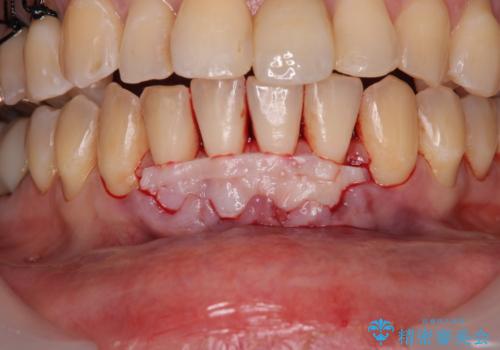

- 他院で矯正治療を終えた結果、下顎前歯の歯肉が退縮してしまい、歯根が見えていることが気になるとのことで来院された患者様です。

歯肉退縮に対して、上顎からの結合組織移植術(CTG)により、歯根の被覆を行うとともに、歯肉の厚みを増すことで将来の退縮リスクを抑制することとしました。